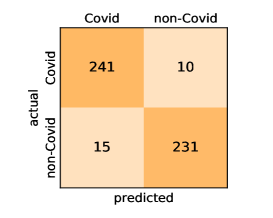

Here, we present and discuss the obtained results for detecting COVID-19 on the considered CT image datasets with different deep networks. We report the quantitative results along with the confusion matrices for every single architecture of the adopted networks.

On the SARS-CoV-2 CT dataset, ResNet101 achieves the best overall performance with respect to almost all evaluation metrics, with an average accuracy and F1-score of and , respectively. The model also achieves an average sensitivity rate of indicating that, on average, only two COVID-19 images are falsely predicted as negatives. It is also powerful enough to correctly identify all Non-COVID-19 cases with only one false positive resulting a specificity rate of . The highest sensitivity score of is achieved by the InceptionV3 model, where only one COVID-19 image is falsely predicted as negative on average. The SqueezeNet model obtains the lowest performance with respect to all evaluation metrics with a fairly acceptable average accuracy and sensitivity scores of and , respectively. Also the ShuffleNet architecture obtains satisfactory performance with approximately improvements on average for all metrics compared with SqueezeNet. Although the results obtained by these models are inferior compared with the rest of models, but they are more efficient. This matches their main objective of reducing the computational costs rather than improving their visual recognition abilities. The rest of models achieve competitive performance and very promising results with slight performance differences. Comparing the different variants of ResNet and DenseNet, we can see that the deeper variants from each architecture yield a slightly better performance. The deeper ResNet101 and ResNeXt101 show a marginal gain in performance compared with their shallower counterparts. The details about class-wise results for each model are summarized in the confusion matrices in Figure 9.

Our models achieve fairly good performance compared with the recently published work using the exact network architectures. This can bet attributed to a better optimization of our models and the effectiveness of our fine-tuning strategy using custom-sized inputs determined specifically for each architecture. Here, we see that DenseNet201 outperforms all other architectures. The model achieves average accuracy and sensitivity scores of and , respectively. It also identifies all COVID-19 images with only four images, on the average, are falsely predicted as Non-COVID-19. DenseNet169 achieves the second best average accuracy of and a very high sensitivity identical to the best model. The DenseNet121 and Xception models have nearly identical results for all evaluation metrics. We observe that small-sized networks such as ResNet18 achieves comparable results with other deeper models. The SqueezeNet and ShuffleNet models perform at a similar level of accuracy. The variants of the ResNeXt models have comparable results and perform as good as the different ResNet variants. A detailed analysis on the class-wise results for individual models is presented in the confusion matrices in Figure 10.